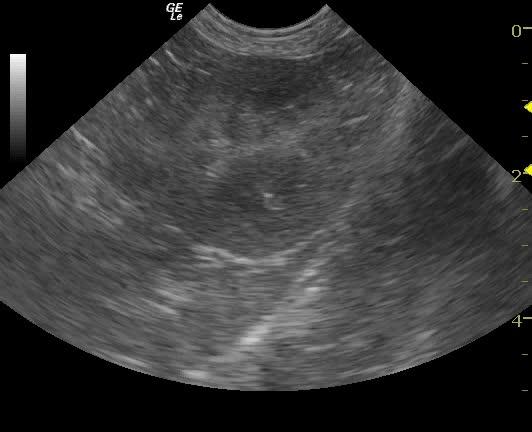

An 11-year-old SF Bichon dog was presented with a history of 3-4 days of lethargy, anorexia, and vomiting. Abnormalities on physical examination were tense abdomen, mild dehydration, and moderate dental tartar. Urinalysis (free-flow sample) showed inappropriate SG, (1.017), hematuria, and, pyuria. Abnormalities on CBC and serum biochemistry were leukocytosis, monocytosis, neutrophilia, azotemia, and hyponatremia.